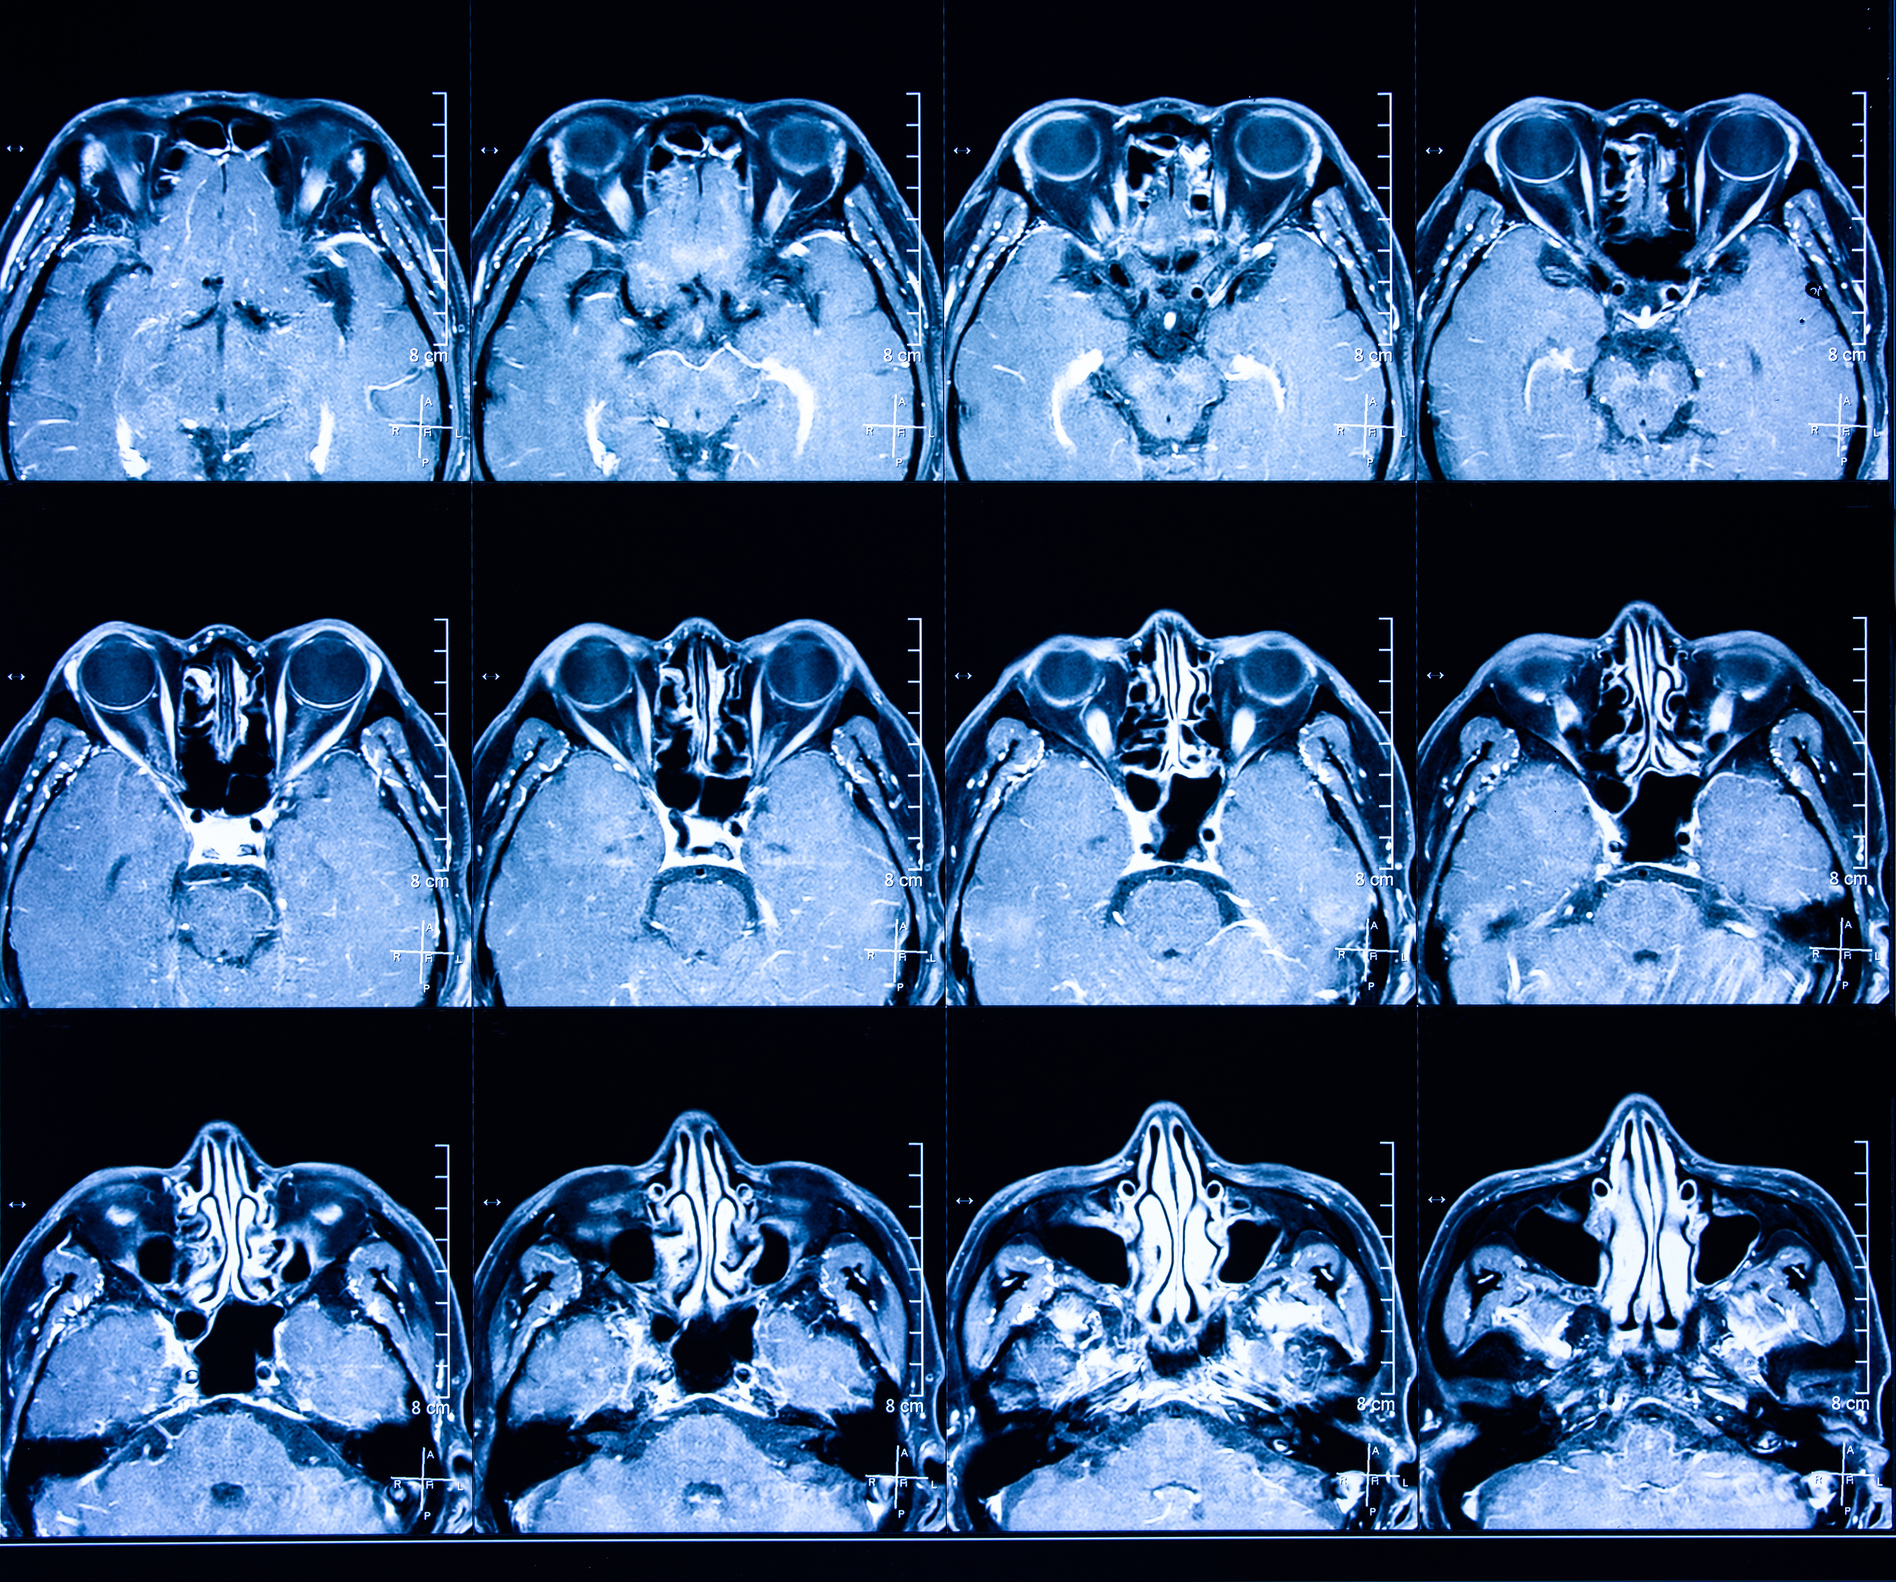

Paranasal Sinus and Nasal Cavity Cancer is a Head and Neck Cancer which occurs when the cells that form mucus within our nose and uppermost respiratory system turn cancerous.

‘Paranasal’ refers to an area around or near the nose, and there are several paranasal sinuses – the frontal sinus, the maxillary sinus, the ethmoid sinus, and the sphenoid sinus. Each of these hollow, air-filled structures are named according to the facial bones which surround them.

The area in which these cancers reside is quite sensitive, with many important nerves, blood vessels, and of course the eye, brain and carotid arteries which supply blood to the brain. Surgery needs to be planned very carefully, maintaining maximum function and appearance of these vital organs and structures. The extent of the surgery and any reconstruction options should be discussed with the treating doctor.